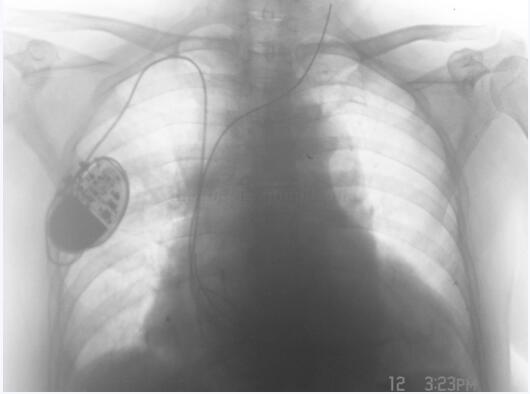

患者,女性,71岁。因“反复畏寒、发热4个月余”于2006年2月19日入院。1996年因心动过缓而安装心脏起搏器于左前胸壁皮下。2005年10月份因发热住院10天,同年12月因发热、左前胸壁安装起搏器处皮肤大面积感染而再次住院,期间将起搏器取出,但起搏电极未取出并固定于颈部皮下,重新放置新起搏器于右前胸壁皮下(图9-3-1)。2006年1月起反复畏寒、发热6次,每4~6天发生一次,最高体温 39.6℃,发热时伴心慌、胸闷。入院前2天再次畏寒、发热,体温 39.5℃,自服“退热药”体温不降而入院。

图9-3-1 胸片显示废弃的心腔内电极以及安置于右胸前起搏器